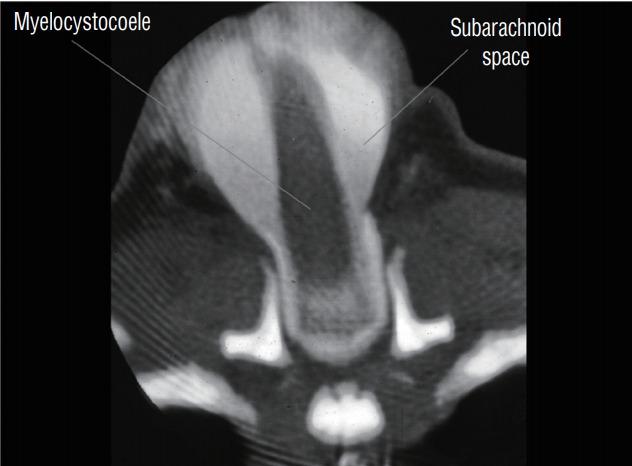

Spinal dysraphic lesions due to focal nondisjunction in primary neurulation are commonly encountered in paediatric neurosurgery, but the "fog-of-war" on these conditions was only gradually dispersed in the past 10 years by the works of the groups led by the senior author and Prof. Kyu-Chang Wang. It is now clear that limited dorsal myeloschisis and congenital spinal dermal sinus tract are conditions at the two ends of a spectrum; and mixed lesions of them with various configurations exist. This review article summarizes the current understanding of these conditions' embryogenetic mechanisms, pathological anatomy and clinical manifestations, and their management strategy and surgical techniques.

由于原发性神经管形成过程中的局灶性不分离导致的脊柱裂病变在小儿神经外科中很常见,但在过去10年中,由资深作者和王宇辰教授领导的团队的工作才逐渐驱散了这些病症上的“战争迷雾”。现在已经明确,有限性背侧脊髓裂和先天性脊柱皮样窦道是同一谱系两端的病症;并且存在各种形态的它们的混合病变。这篇综述文章总结了目前对这些病症的胚胎发生机制、病理解剖和临床表现,以及它们的治疗策略和手术技术的认识。